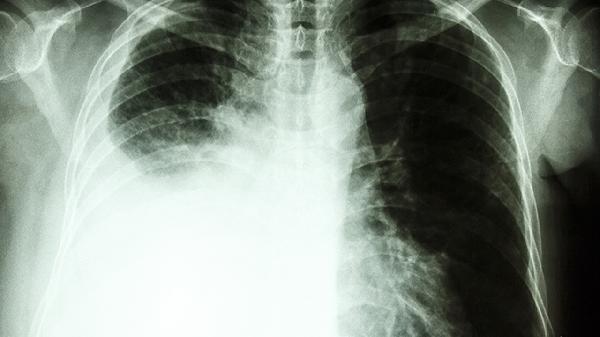

肺部密度影是怎么回事

肺部密度影可能由肺炎、肺结核、肺结节、肺纤维化、肺部肿瘤等原因引起,可通过胸部CT检查、病理活检、实验室检查等方式明确诊断。建议及时就医,在医生指导下进行针对性治疗。